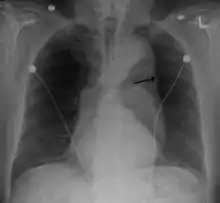

Thoracic aortic aneurysm

A thoracic aortic aneurysm is an aortic aneurysm that presents primarily in the thorax.

A thoracic aortic aneurysm is the "ballooning" of the upper aspect of the aorta, above the diaphragm. Untreated or unrecognized they can be fatal due to dissection or "popping" of the aneurysm leading to nearly instant death. Thoracic aneurysms are less common than an abdominal aortic aneurysm.[2] However, a syphilitic aneurysm is more likely to be a thoracic aortic aneurysm than an abdominal aortic aneurysm. This condition is commonly treated via a specialized multidisciplinary approach with both vascular surgeons and cardiac surgeons.